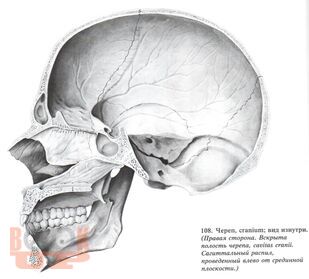

В учебном пособии представлены широкие возможности лучевых методов исследования при патологии области турецкого седла. Большое внимание уделено возможности классической краниографии с учетом новых современных аппаратов, таких как МРТ И КТ.

Подробно представлена классификация опухолей турецкого седла, их частота, клинические проявления с учетом физиологии гипофиза. Наряду с общепринятой классификацией с делением опухолей гипофиза на эозонофильные, хромофобные и базофильные варианты рекомендуется более современная классификация с делением аденом гипофиза по гормональной активности. Кратко даны возможности современных методов лечения опухолей области турецкого седла. Ценным являются представления о около селлярной локализации опухолей по топографической и гистологической структуре и генезу.

Методическое учебное пособие иллюстрировано снимками, схемами, дан краткий список литературы. Учебное пособие предназначено для интернов, ординаторов, рентгенологов.